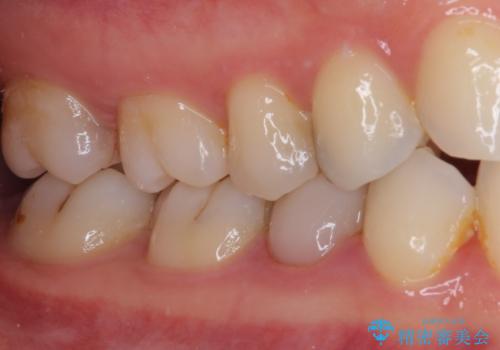

- 神経を抜く処置の後に装着したプラスチックのクラウンが外れてしまったとのことで来院された患者様です。

患者様自身、神経の取り除かれた歯はしっかりと製作されたクラウンを装着するべきと理解していただいていたため、オールセラミッククラウンにて補綴治療することとしました。

丈夫なクラウンを装着できただけでなく、形態や色調も自然に仕上げることができました。